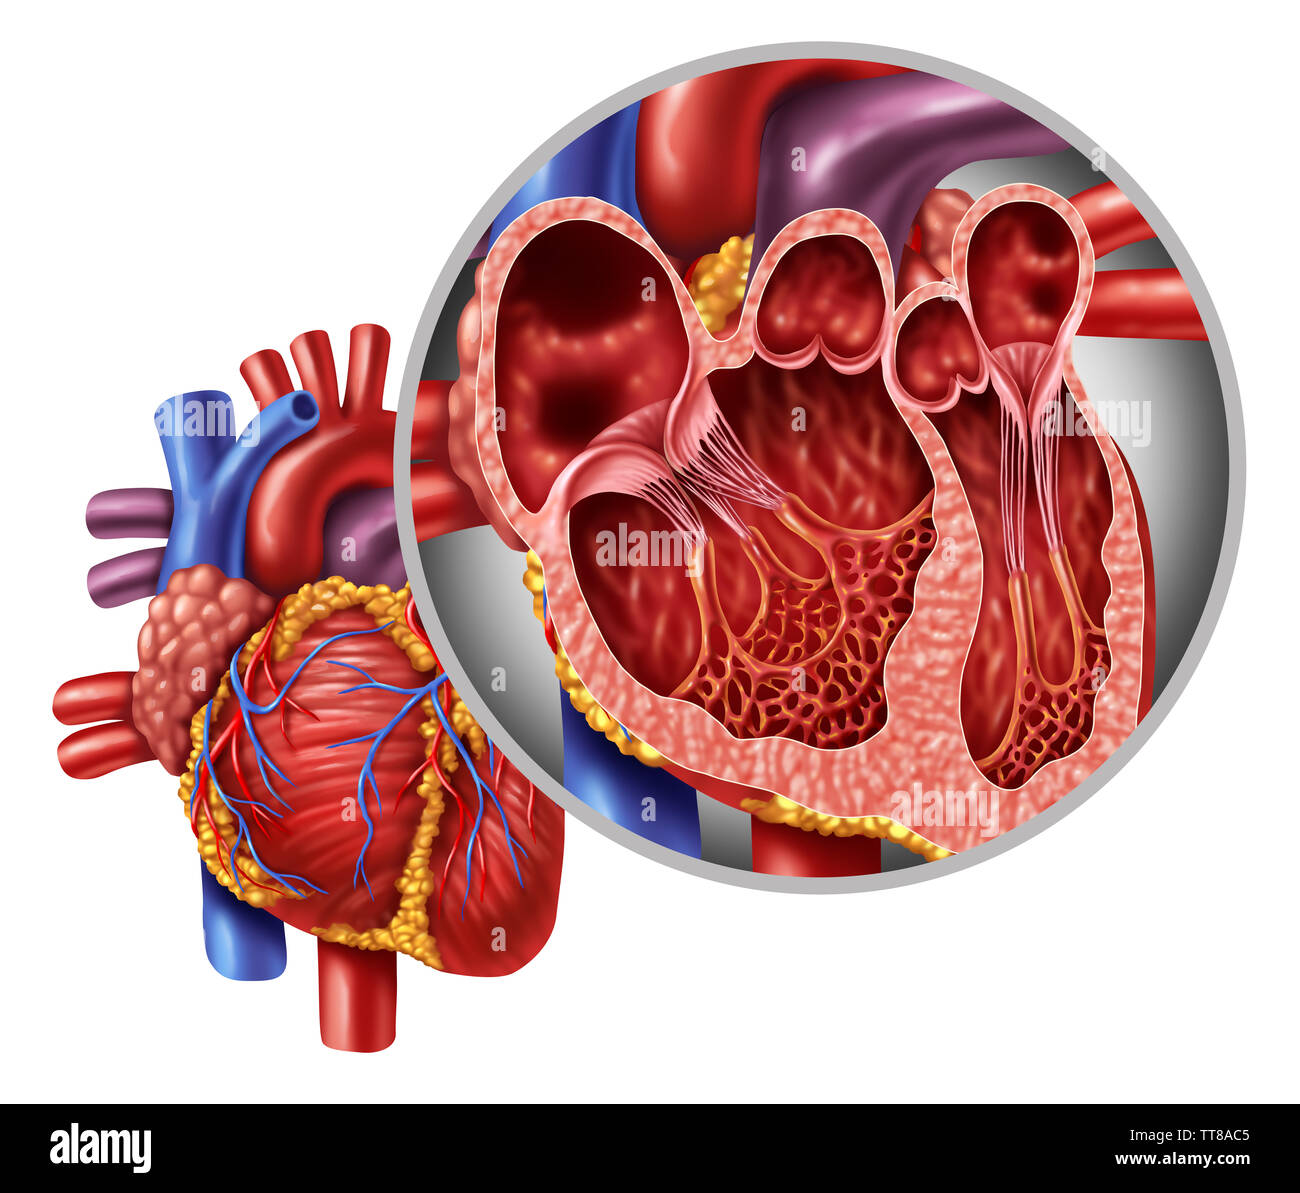

Human heart anatomy close up diagram concept from a healthy body isolated on white background as a medical health care symbol. Stock Photohttps://www.alamy.com/image-license-details/?v=1https://www.alamy.com/human-heart-anatomy-close-up-diagram-concept-from-a-healthy-body-isolated-on-white-background-as-a-medical-health-care-symbol-image255880693.html

Human heart anatomy close up diagram concept from a healthy body isolated on white background as a medical health care symbol. Stock Photohttps://www.alamy.com/image-license-details/?v=1https://www.alamy.com/human-heart-anatomy-close-up-diagram-concept-from-a-healthy-body-isolated-on-white-background-as-a-medical-health-care-symbol-image255880693.htmlRFTT8AC5–Human heart anatomy close up diagram concept from a healthy body isolated on white background as a medical health care symbol.